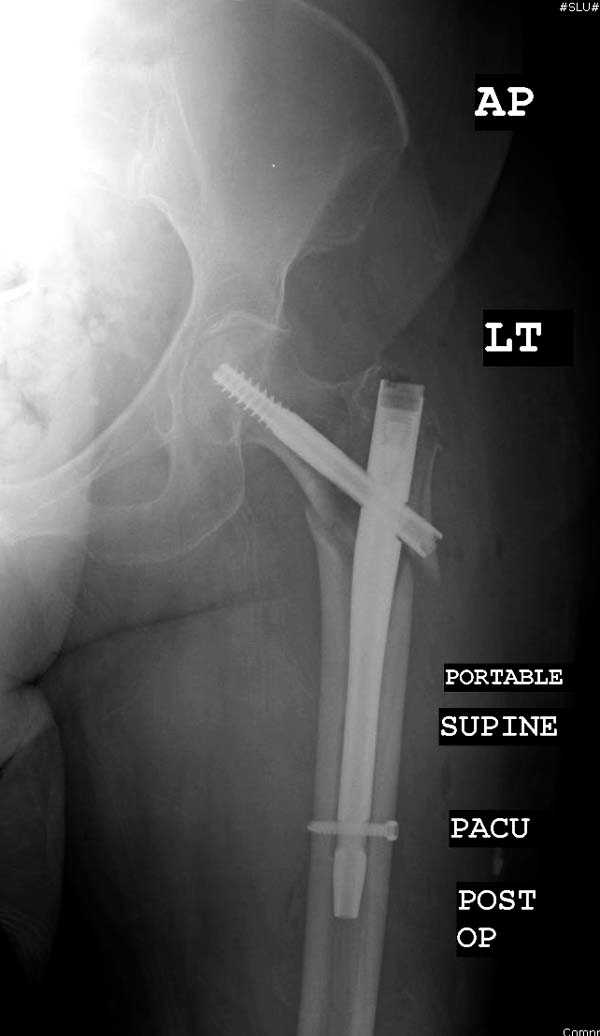

Здесь представлен случай, где в послеоперационном периоде обнаружена техническая ошибка, Gamma 3 установлен с нарушением методики. Больная в 91 лет, прооперирована через день после поступления и выписана через 48 часов.

При первом послеоперационном поликлиническом осмотре больная предъявила жалобы на боли в бедре. В серийных снимках обнаружен продольный перелом верхнего отдела бедра.

Считаем, что техническая ошибка произошла во время установки гвоздя, когда рассверливанию канала не уделили должного внимания. Канал остался узковат, и гвоздь был забит с силой. Полная нагрузка конечности приостановлена на две недели, и боли в конечности изчезли. Больная начала нагрузку и перелом срастается.-- Djoldas Kuldjanov, M.D.Associate ProfessorDepartment of Orthopedic SurgerySt. Louis University